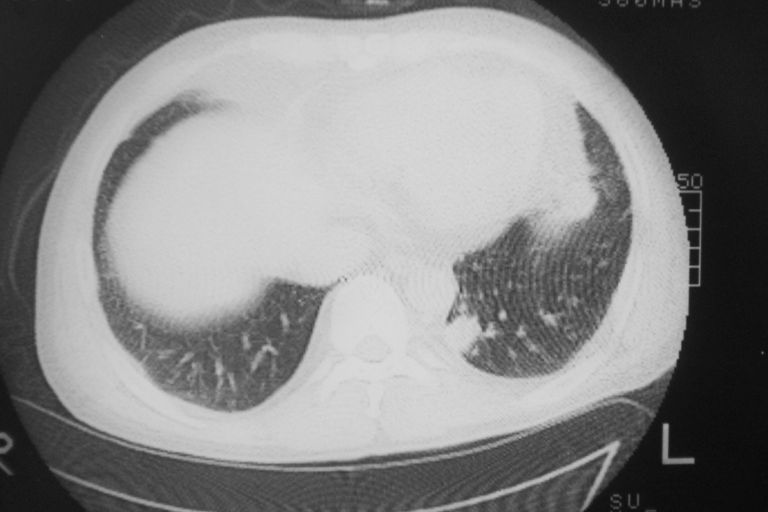

标题: CT10574:男 50岁胸部CT请会诊!

患者 男 50岁 无痛性咯血3天,无其他不适.

左下肺结节状软组织密度影,边缘有毛刺,考虑周围型肺癌。

1 左肺下叶基底段见两结节软组织密度灶, 肺窗边缘见有毛刺征像, 不能排除占位. 2 建议结合临床治疗一周后ct随访在看其结果.

临近胸膜增厚,病变周围肺不清,稍有分叶。结节密度略高,肺、纵隔窗差异不大,肺癌待排。前方还有一个

左下肺结节状软组织密度影,一个边缘有卫星病灶,邻近胸膜增厚.另一个有毛刺.心影周围水样密度影环绕.考虑:

1.肺癌可能.肺tb待排.

2.左侧胸膜增厚.心包积液.